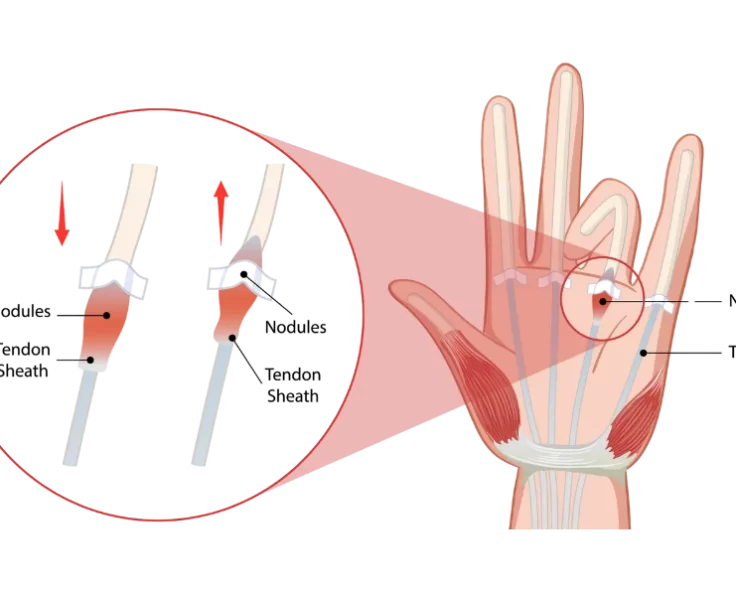

Trigger Finger Release

Trigger finger develops when the tendons that flex your fingers become inflamed, producing finger soreness and pain.